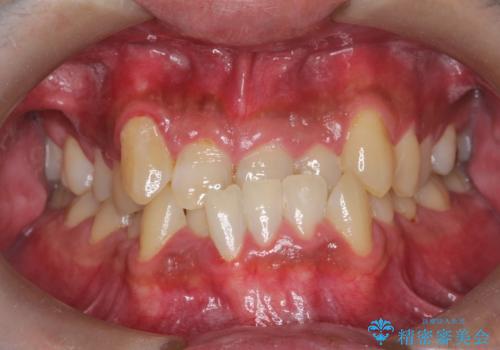

- 主訴:上の歯列の空隙を閉じたい

上顎前歯部に空隙が目立ちました。ワイヤー矯正、インビザライン(マウスピース矯正)どちらの方法でも適用症例と説明し、ワイヤー矯正治療(審美装置)を希望されました。

上顎歯列の空隙を閉じるのと一緒に、ディープバイト気味の被蓋も下顎前歯の圧下を行い改善しました。